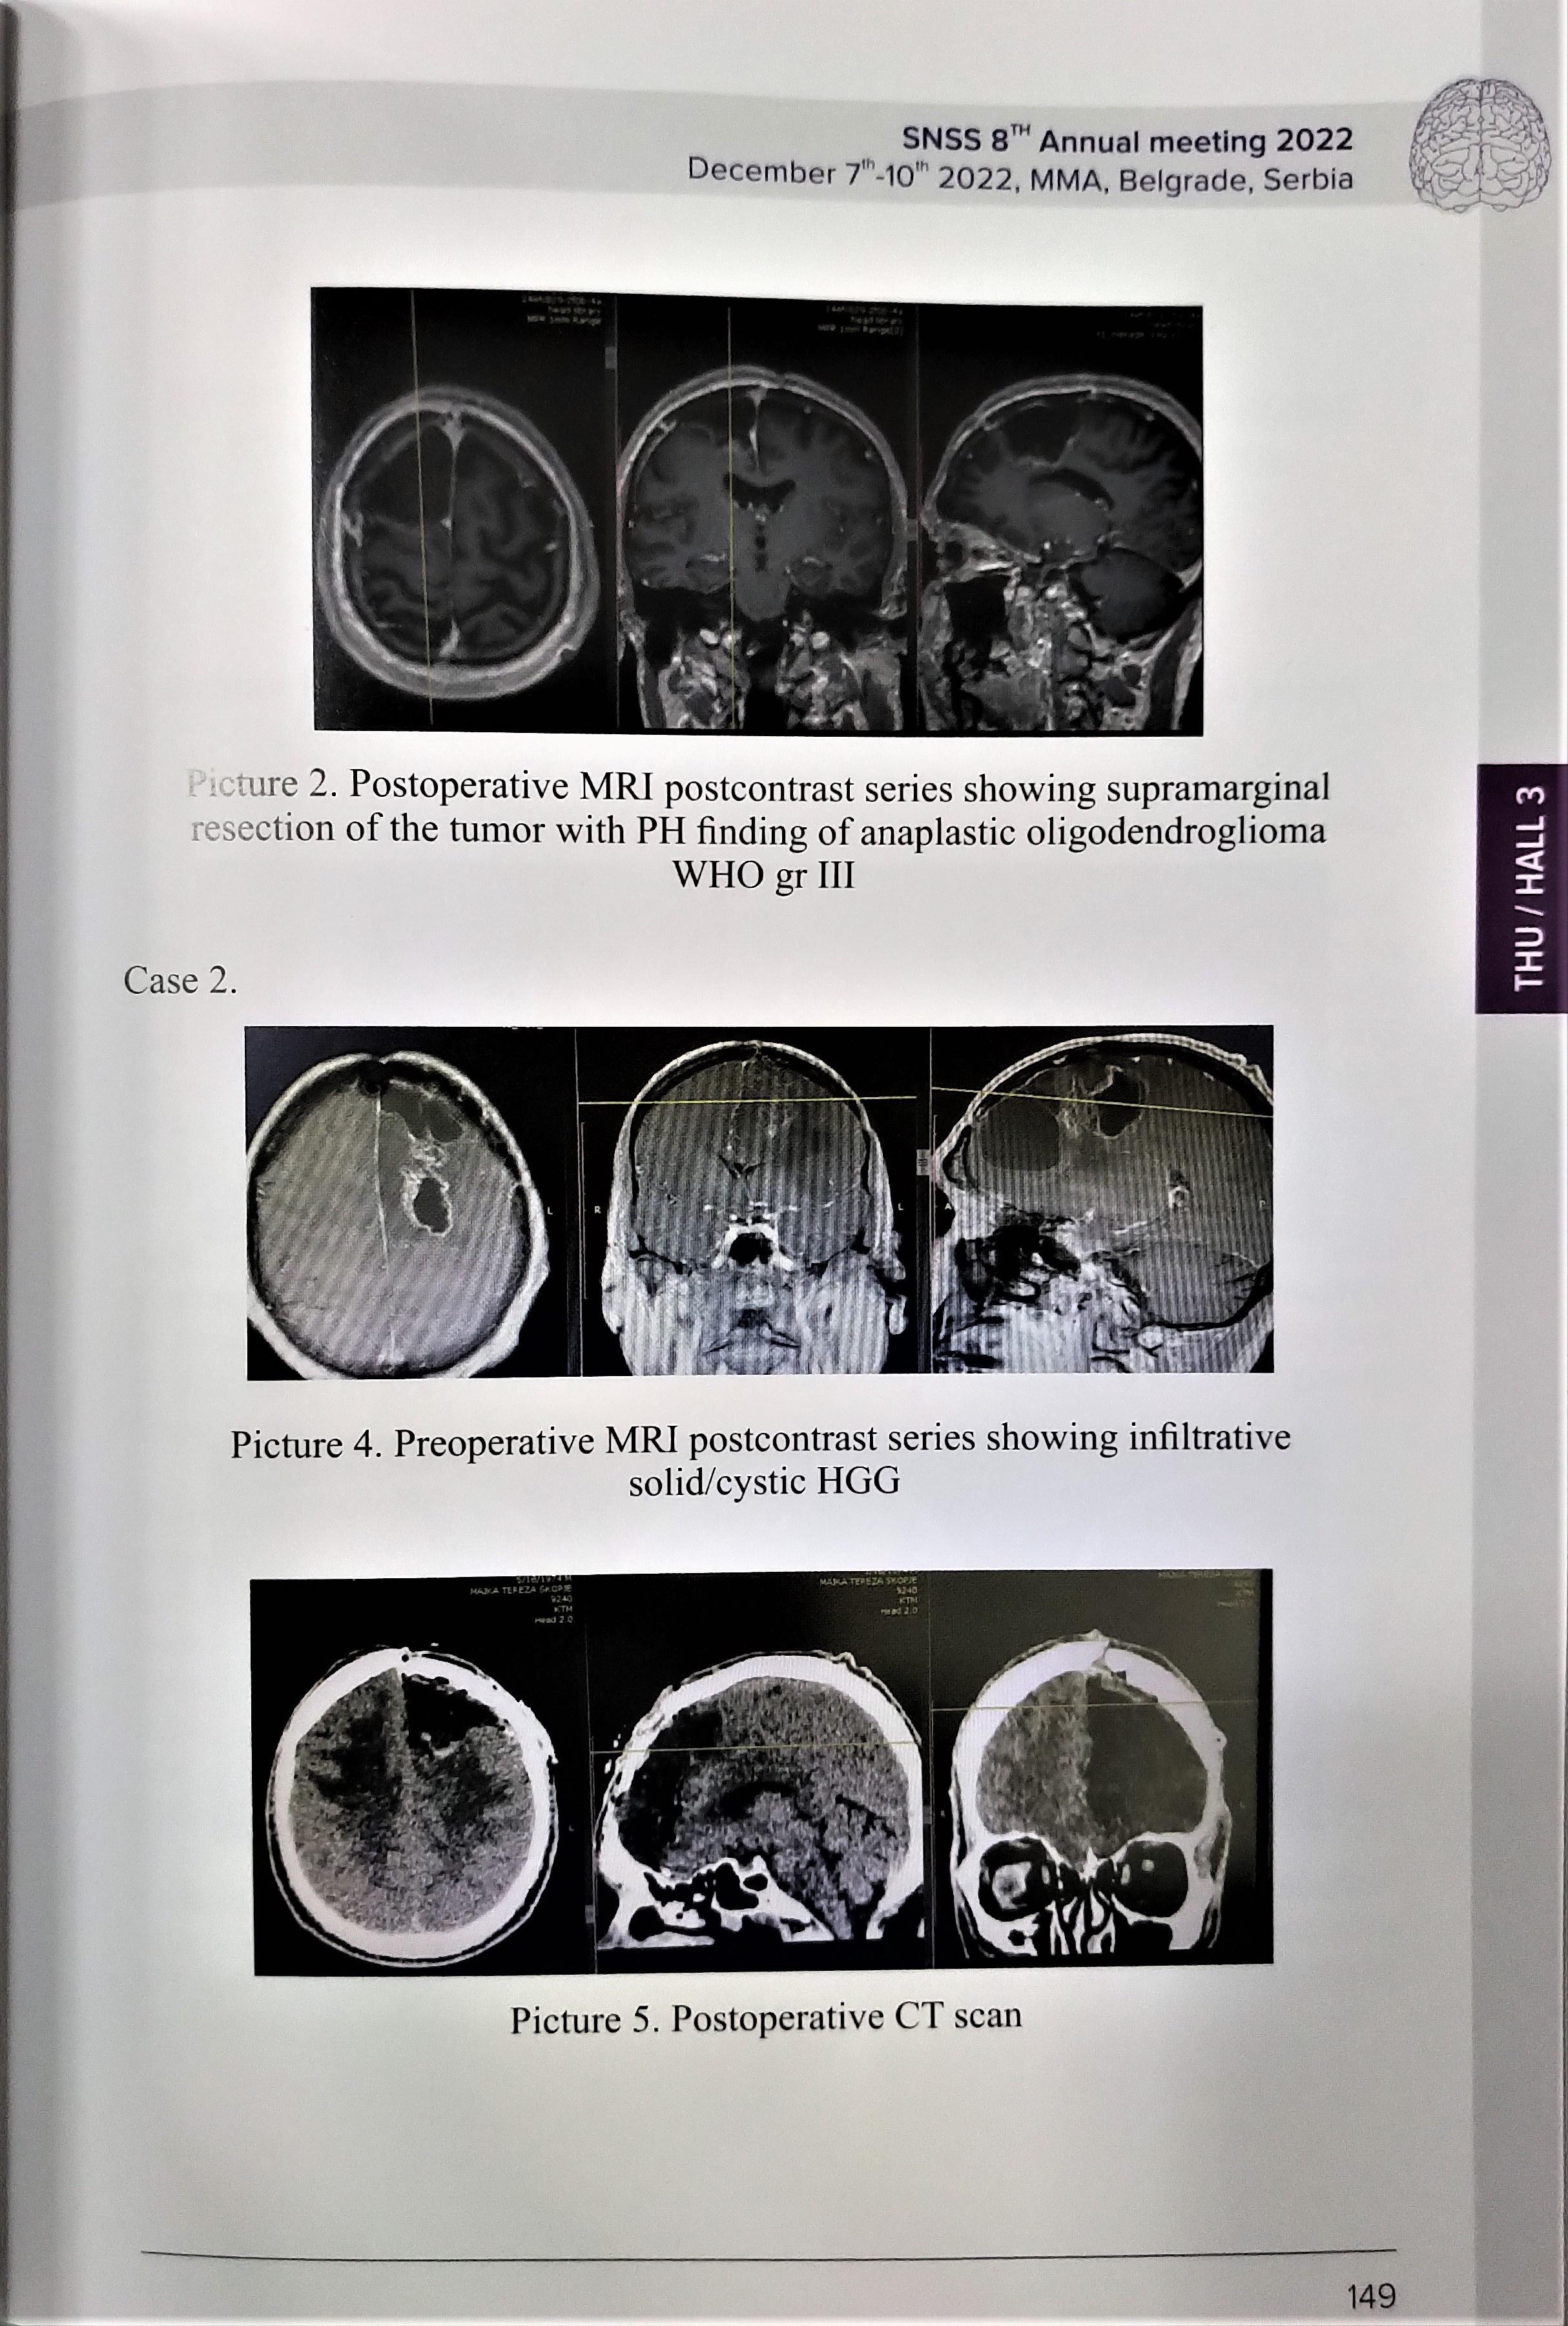

Role of the intraoperative fluorescence in the extent of surgical resection of high-grade gliomas on prediction of clinical outcome and progression free survival.Case series